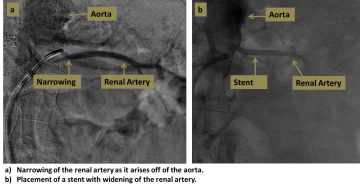

A stent graft consists of a tube of metallic mesh with an impermeable fabric covering. The impermeable covering prevents leakage of blood or bile out through the stent, and prevents ingrowth of tissue into the stent. This may help keep the stent graft open. In cases of aneurysm or dissection of the aorta or other vessels, the stent graft can serve to repair the diseased vessel without resorting to open surgery.

An interventional radiologist accesses the arterial or biliary system and navigates into the target vessel. The stent graft is then deployed in the area of abnormality, effectively creating an artificial bypass that excludes the abnormality and restores flow through the vessel.